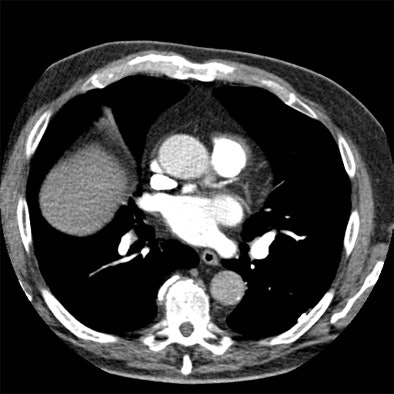

| Axial images of the thorax above and below were created from a pulmonary embolism study acquired in 0.2 seconds at dual-source CT in Flash mode, using the P3T algorithm to create the contrast injection protocol. The pulmonary and segmental arteries are well-enhanced (> 300 HU), with adequate enhancement in the aorta. The contrast protocol was created based on the patient's weight, scan duration, contrast concentration, and time to peak of a 15-mL timing bolus. This patient received 68 mL of 370 mgI/mL contrast at 5.2 mL per second. (A mixture phase of 35 mL, 20% contrast, was followed by a saline flush of 40 mL, all at the same flow rate.) Images courtesy of J. Michael Barraza. |